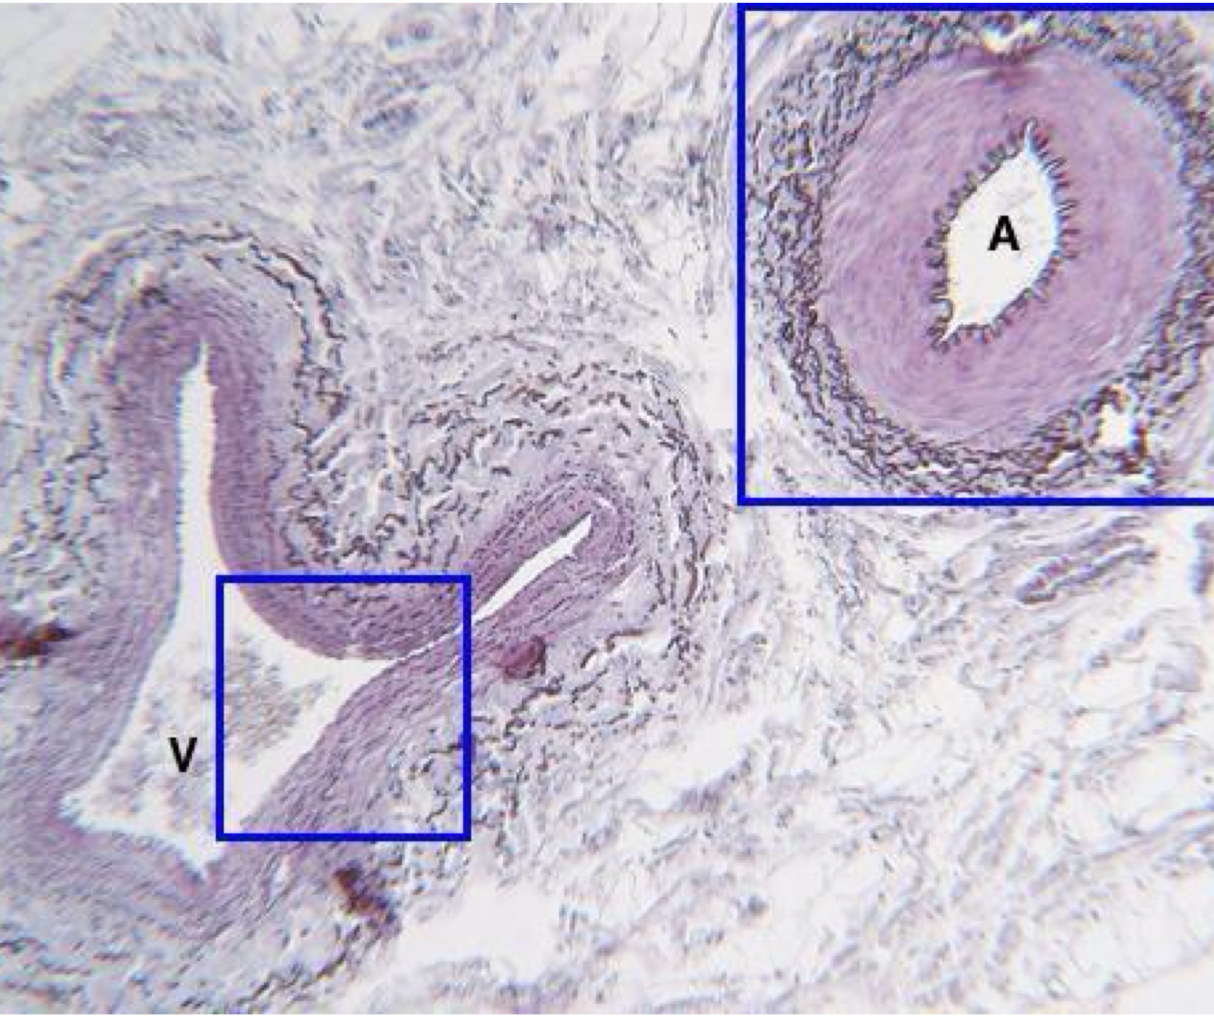

what is being shown on the right **

artery

what is being shown on the left **

vein

arteries have

large lumen

thick vessel walls

veins are composed of

collagen, little smooth muscle and elastin

veins have

thinner vascular wall